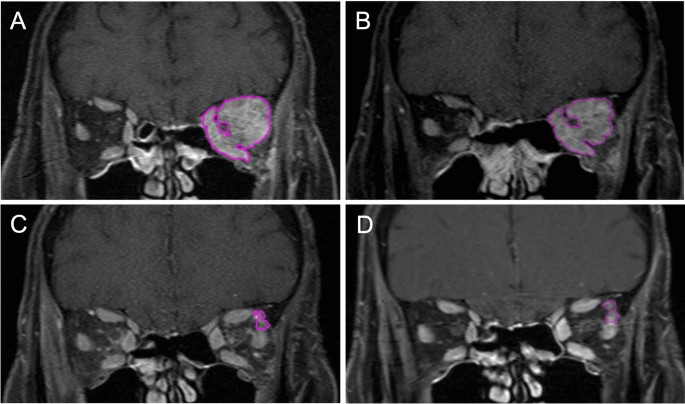

All lesions were detectable on both T1 and T2 weighted sequences before treatment. Lymphoma lesions were either iso- (76.3%) or hyperintense (23.7%) on pre-treatment T1 weighted images. Shortly after irradiation (< 6 months), residues were still detectable on T1 weighted images in 91.2% of all patients. However, at that time point in 29.4% of the cases no residue could be detected on T2 weighted images. In general, T1 weighted images showed higher detection rates for tumor residues than the T2 weighted images. We therefore decided to perform all volumetric analyses on T1-weighted images. Figure 1 shows an exemplary MRI set.

Patient with orbital MALT lymphoma before (A) and 2 (B), 15 (C) and 40 (D) months after irradiation. The well definable tumor residue is marked in magenta.